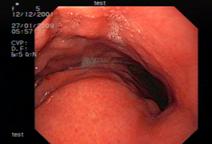

Неэпителиальные опухоли. В IV группе из 42 пациентов с визуальным диагнозом неэпителиального новообразованиями особую трудность в дифференциальной диагностике представляли опухоли, имеющие воспалительные изменения, изъязвления, сращения со слизистой оболочкой или её прорастания. Основным отличительным признаком неэпителиального образования являлась гипоэхогенная опухоль, исходящая из мышечного слоя, мышечной пластинки слизистой оболочки или расположенная на её границе с подслизистым слоем. Слизистый слой над опухолью истончен и четко прослеживался (рис.5).

Рис. 5. 48 лет. Неэпителиальная опухоль желудка.

Заключение иммуногистохимии - GIST: а - визуальная картина неэпителиальной опухоли с признаками прорастания слизистой оболочки; б - эндосонограмма гипоэхогенной неоднородной неэпителиальной опухоли, исходящей из мышечного слоя, с анэхогенными включениями.